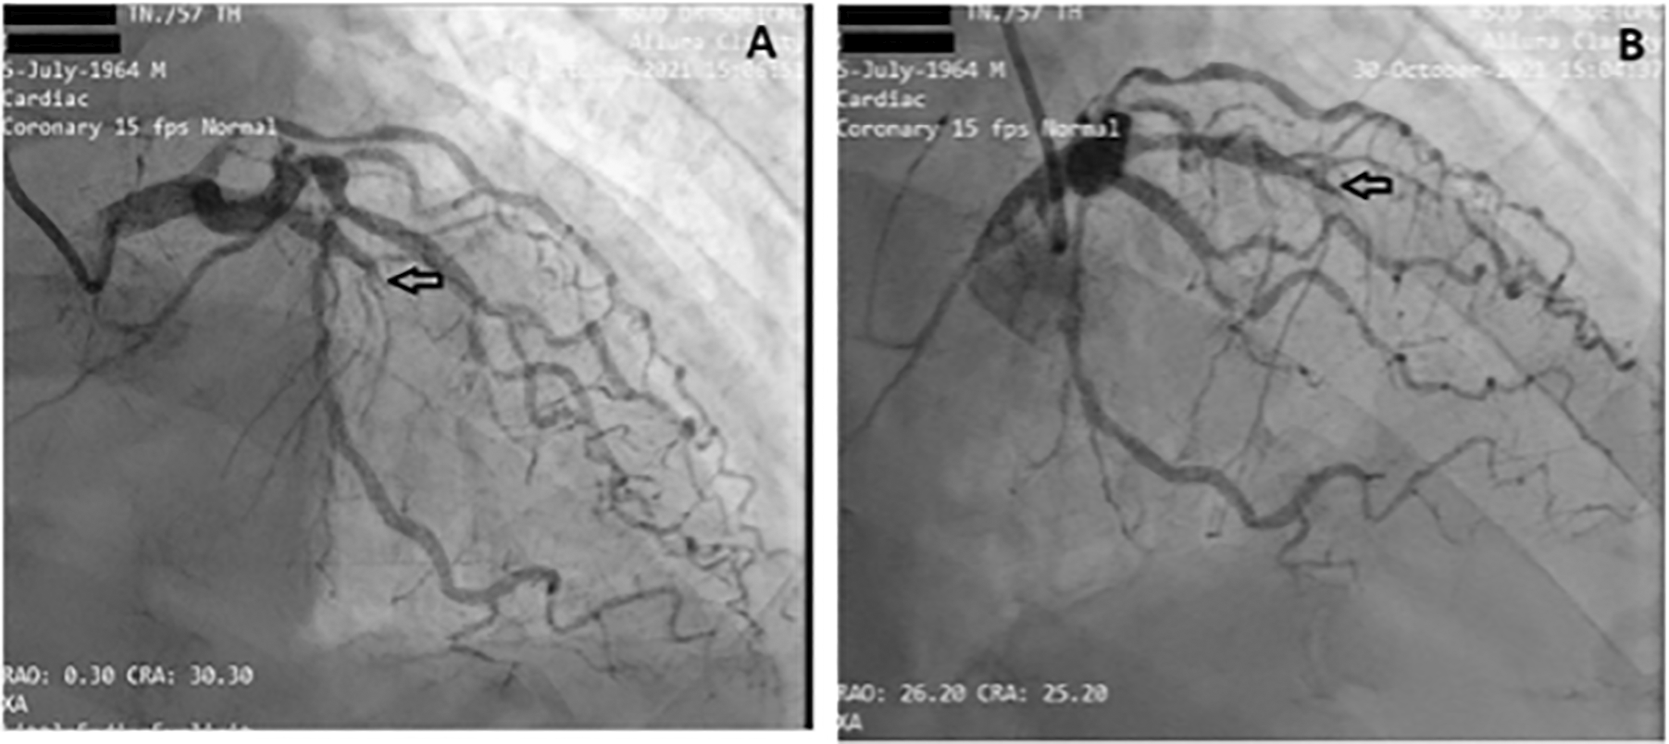

Before the invasive strategy was done, the patient had another ECG eight hours after the first ECG, based on the second (Figure 2). The ECG showed ST-segment elevation changes that were greater than 1 mm. The early invasive strategy (Figure 3 and Figure 4; Extended data: Video 1 and Video 2)3,4 showed that the left anterior descending artery (LAD) had total occlusion of 100% in the middle LAD (Figure 3). The left circumflex artery (LCx) had non-significant stenosis of 40% proximal and 65% distal, and right coronary artery (RCA) had non-significant stenosis of 55% distal. The RCA had grade 2 collateral arteries that supply blood to the mid LAD (Figure 4).

The left circumflex artery (LCx) had non-significant stenosis of 40% proximal and 65% distal LCx.